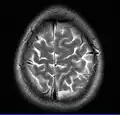

Cross-sectional T1-weighted MRI of a healthy human brain acquired with an ultra high-field MR of 7 Tesla field strength

This axial T2-weighted (CSF white) MR scan shows a normal brain at the level of the lateral ventricles.